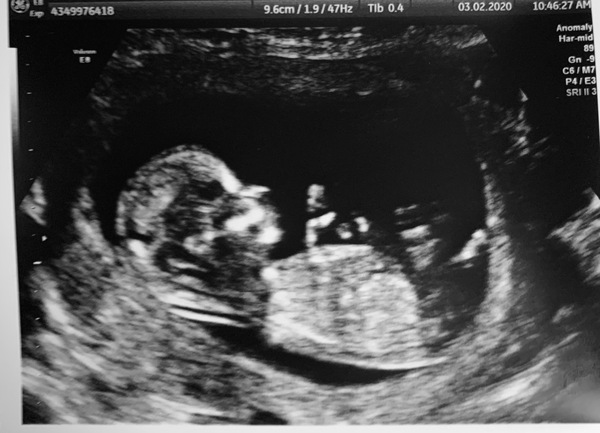

Hi All, scan went very well. 12 weeks today, baby due 20th August. We are over the moon and very excited.

Hope you don't mind me joining. From going through 1 MC and 3 MMC we finally have our sticky little miracle 💗 We had our 12 week scan yesterday and saw a very happy baby with a good heartbeat and I was put at 12+4 so due 20th August. Congratulations to all you other ladies who have got positive BFP's and have had perfect scans and I keep everything crossed for happy and healthy pregnancies.